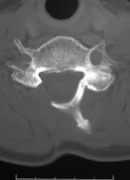

従来の手術では医師の経験によって手術成績にばらつきがあるという問題がありましたが、当院ではO-arm 2やロボットCアームなどの最先端の手術支援機器を導入することで、安全性の向上に注力しています。これに加えて、通常のナビゲーションに加えて術中3D画像撮影が可能な機器も活用しています。

また、頚椎症性脊髄症や側弯症などの疾患に対しては、最新の設備を駆使して手術を行っています。具体的には、CTナビゲーションや脊髄刺激モニタリング、自己回収輸血などを利用して、安全性に配慮した手術を実施しています。また、新しいインプラントの導入により、人間の本来の弯曲に近い矯正術が可能となっています。